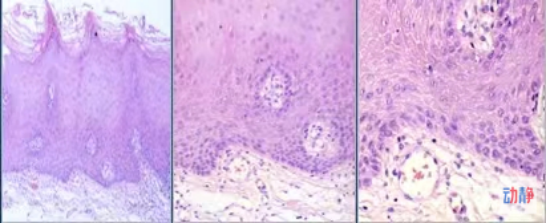

烟斑的形成不仅会影响美观,而且会让更多结石和软垢沉积,烟雾中的化学成分可直接刺激局部牙周组织,长期刺激可使牙龈发生慢性炎症。下图是烟斑在显微镜下的样子!